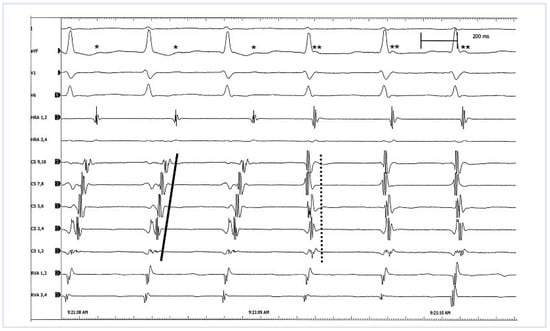

In this patient, recurrent tachycardia occured since infancy and she had to undergo medical conversion with adenosine at the age of 6 weeks and 2 years, respectively. Prophylactic antiarrhythmic therapy with propranolol was given for one year. The patient remained asymptomatic until the age of 13 years. The tachycardia occurred again with increasing frequency and intensity thereafter. The ECG of a recent episode showed a narrow complex tachycardia at a rate of 150 beats per minute. Our differential diagnosis was AV nodal reentrant tachycardia and AV reentrant tachycardia. The age and gender of the patient as well as the symptoms with “pulsations at the neck” suggests an AV nodal reentrant tachycardia while the early onset of the tachycardia in infancy is more typical for an AV re-entrant tachycardia. The patient was brought forward for an electrophysiology study with the aim to either modulate the slow pathway of the AV node or to ablate the accessory pathway. With programmed atrial stimulation, with a singular extrastimulus (S1S1 500 ms, S1S2 340 ms), the tachycardia could be induced; the surface ECG is shown in Figure 1.

Figure 1. lead surface ECG during electrophysiological study with induction of the tachycardia, see text (speed 50 mm/s).

The surface ECG in Figure 1 shows a regular tachycardia with narrow QRS complexes at a rate of 152 bpm. The tachycardia starts after programmed stimulation in the right atrium. Stimulation traces in the atrial drive train (S1) can be identified, preceeding each P wave, in the first 3 beats. Then, after the atrial extrastimulus (S2), the tachycardia is induced. The first 3 beats of the tachycardia (QRS complexes N° 4 to 6) are followed by a small biphasic P wave with a long R-P interval of 154 ms, best seen within the ST segment in II and aVF (*). Later (from QRS complex N° 6 onwards), the P wave is just behind the QRS complex with a short R-P interval of 52 ms, suggesting a short retrograde activation (**). The explanation for this phenomenon can be seen in the intracardiac leads (Figure 3): The induced tachycardia is an orthodromic AV re-entrant tachycardia with antegrade conduction over the AV node and retrograde conduction over a left lateral accessory pathway (concealed Wolff Parkinson White Syndrome). The earliest retrograde activation of the atrium is seen in the distal coronary sinus (CS 1, 2 and CS 3, 4). The activation then spreads over the atria and reaches the high right atrium relatively late (solid line). After 3 beats of tachycardia, there is a complete change in the activation pattern and a typical (slow-fast) AV nodal reentrant tachycardia is induced. The earliest atrial activation occurs at the coronary sinus ostium (CS 7, 8 and CS 9, 10) and retrograde atrial activation occurs almost simultaneously with the antegrade ventricular activation (dotted line).

Figure 3. Simultaneous intracardiac leads corresponding to Figure 2 with catheters positioned in the right atrium (HRA), the coronary sinus (CS 1,2 = proximal, CS 9,10 = distal) and the right ventricle (RVA) (speed 100 mm/s).